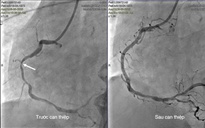

Tại đây, bệnh nhân được chụp mạch vành khẩn cấp và phát hiện có nhiều huyết khối gây tắc động mạch vành phải, là nguyên nhân chính gây ngưng tim trước nhập viện. Bệnh nhân nhanh chóng được đặt stent mạch vành và tiếp tục duy trì tuần hoàn ngoài cơ thể. Hiện tại, bệnh nhân tỉnh táo, tiếp tục được theo dõi sát.